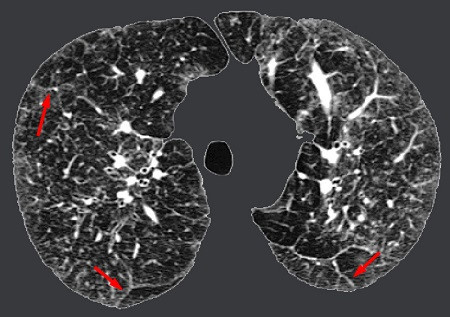

| Tổn thương bệnh phổi kẽ trên phim chụp cắt lớp. |

Trên phim chụp Xquang, chụp cắt lớp vi tính, có thể thấy hình ảnh tổn thương của phổi. Nội soi phế quản thấy tổn thương giúp ích cho chẩn đoán bệnh. Trong xét nghiệm chức năng phổi (PFTs) hoặc cho bệnh nhân tập thể dục thử nghiệm sẽ thấy các triệu chứng của bệnh phổi kẽ nặng lên khi hoạt động. Từ đó bác sĩ có thể đánh giá chức năng phổi.